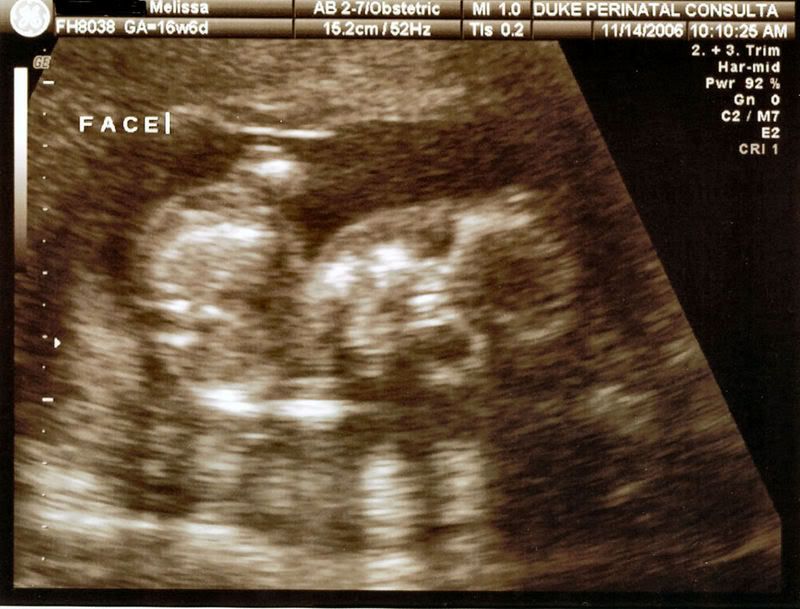

My daughter had her 18 week ultrasound today and we have a little boy. He was quite proud to display his little tallywhacker at the appropriate moment. We are so thrilled and tickled that he seems very happy and healthy. As soon as I get the pictures loaded onto photo bucket I will post the handsome little devils pictures. |

here he is asleep http://i11.photobucket.com/albums/a190/the...b4fan/Sleep.jpg from the side with his little hand open http://i11.photobucket.com/albums/a190/the...an/openhand.jpg Here is his little face http://i11.photobucket.com/albums/a190/the...4fan/Face-1.jpg He had ginormous feet http://i11.photobucket.com/albums/a190/the...ab4fan/Foot.jpg His defining moment http://i11.photobucket.com/albums/a190/the...fab4fan/Boy.jpg |